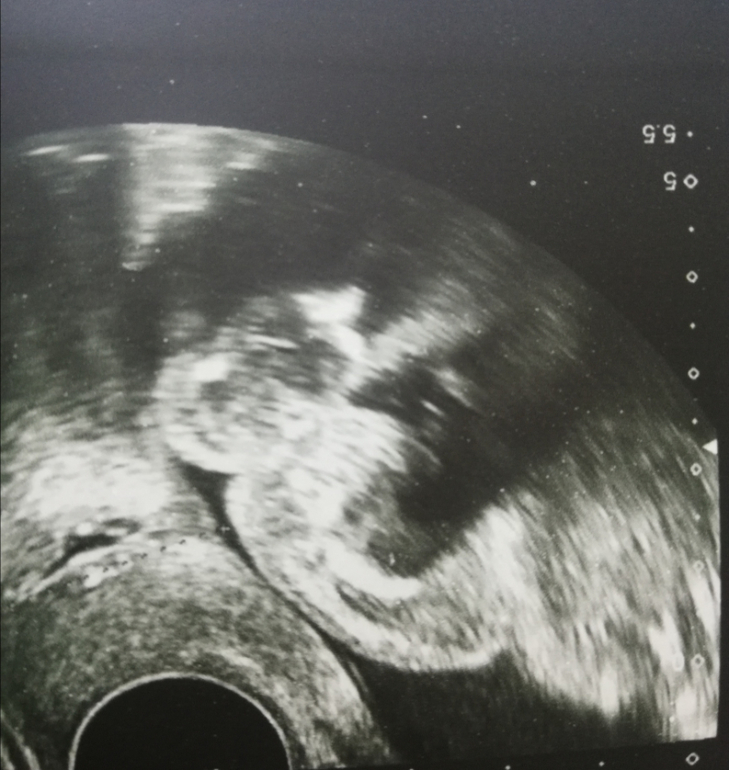

УЗИ, КТГ, доплерВчера был долгожданный 2й скрининг. Урвала пару фоточек на память

По части развития малыша все хорошо.